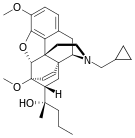

Oripavine derivatives

Thienorphine

- 7-PET

- Acetorphine

- Alletorphine (N-allyl-noretorphine)

- BU-48

- Buprenorphine

- Buprenorphine-3-glucuronide

- Cyprenorphine

- Dihydroetorphine

- Etorphine

- Homprenorphine

- 18,19-Dehydrobuprenorphine (HS-599)

- N-cyclopropylmethylnoretorphine

- Nepenthone

- Norbuprenorphine

- Norbuprenorphine-3-glucuronide

- Thevinone

- Thienorphine

Structures

| Oripavine derivatives | ||||

7-PET 7-PET |

Acetorphine Acetorphine |

Alletorphine Alletorphine |

BU-48 BU-48 |

Buprenorphine Buprenorphine |

Cyprenorphine Cyprenorphine |

Dihydroetorphine Dihydroetorphine |

Etorphine Etorphine |

Homprenorphine Homprenorphine |

18,19-Dehydrobuprenorphine 18,19-Dehydrobuprenorphine |

N-cyclopropylmethylnoretorphine N-cyclopropylmethylnoretorphine |

Nepenthone Nepenthone |

Norbuprenorphine Norbuprenorphine |

Thevinone Thevinone |

Thienorphine Thienorphine |